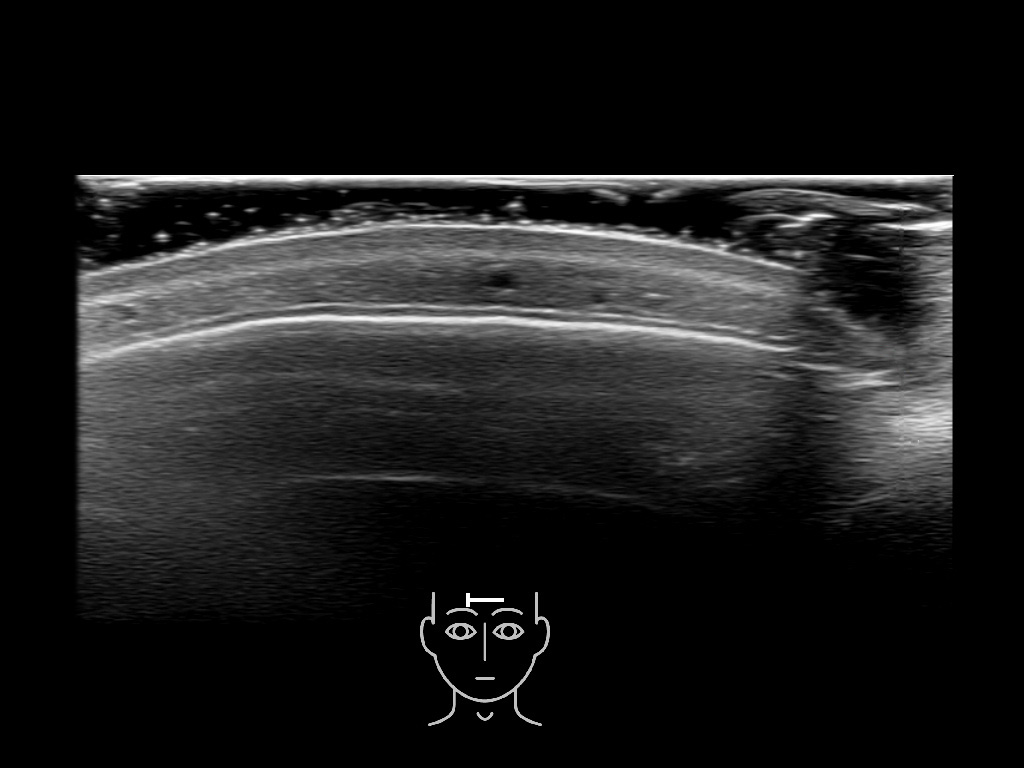

In this section you will learn more about the different layers of the face with the use of ultrasound. When you click on the secondary ultrasound image, you will see the different structures as an overlay. This will help to train yourself to recognize the different layers of the face.

Study the first image to recognize the different layers. If you are sure about the layers, swipe to the second image to view the answer (if applicable).